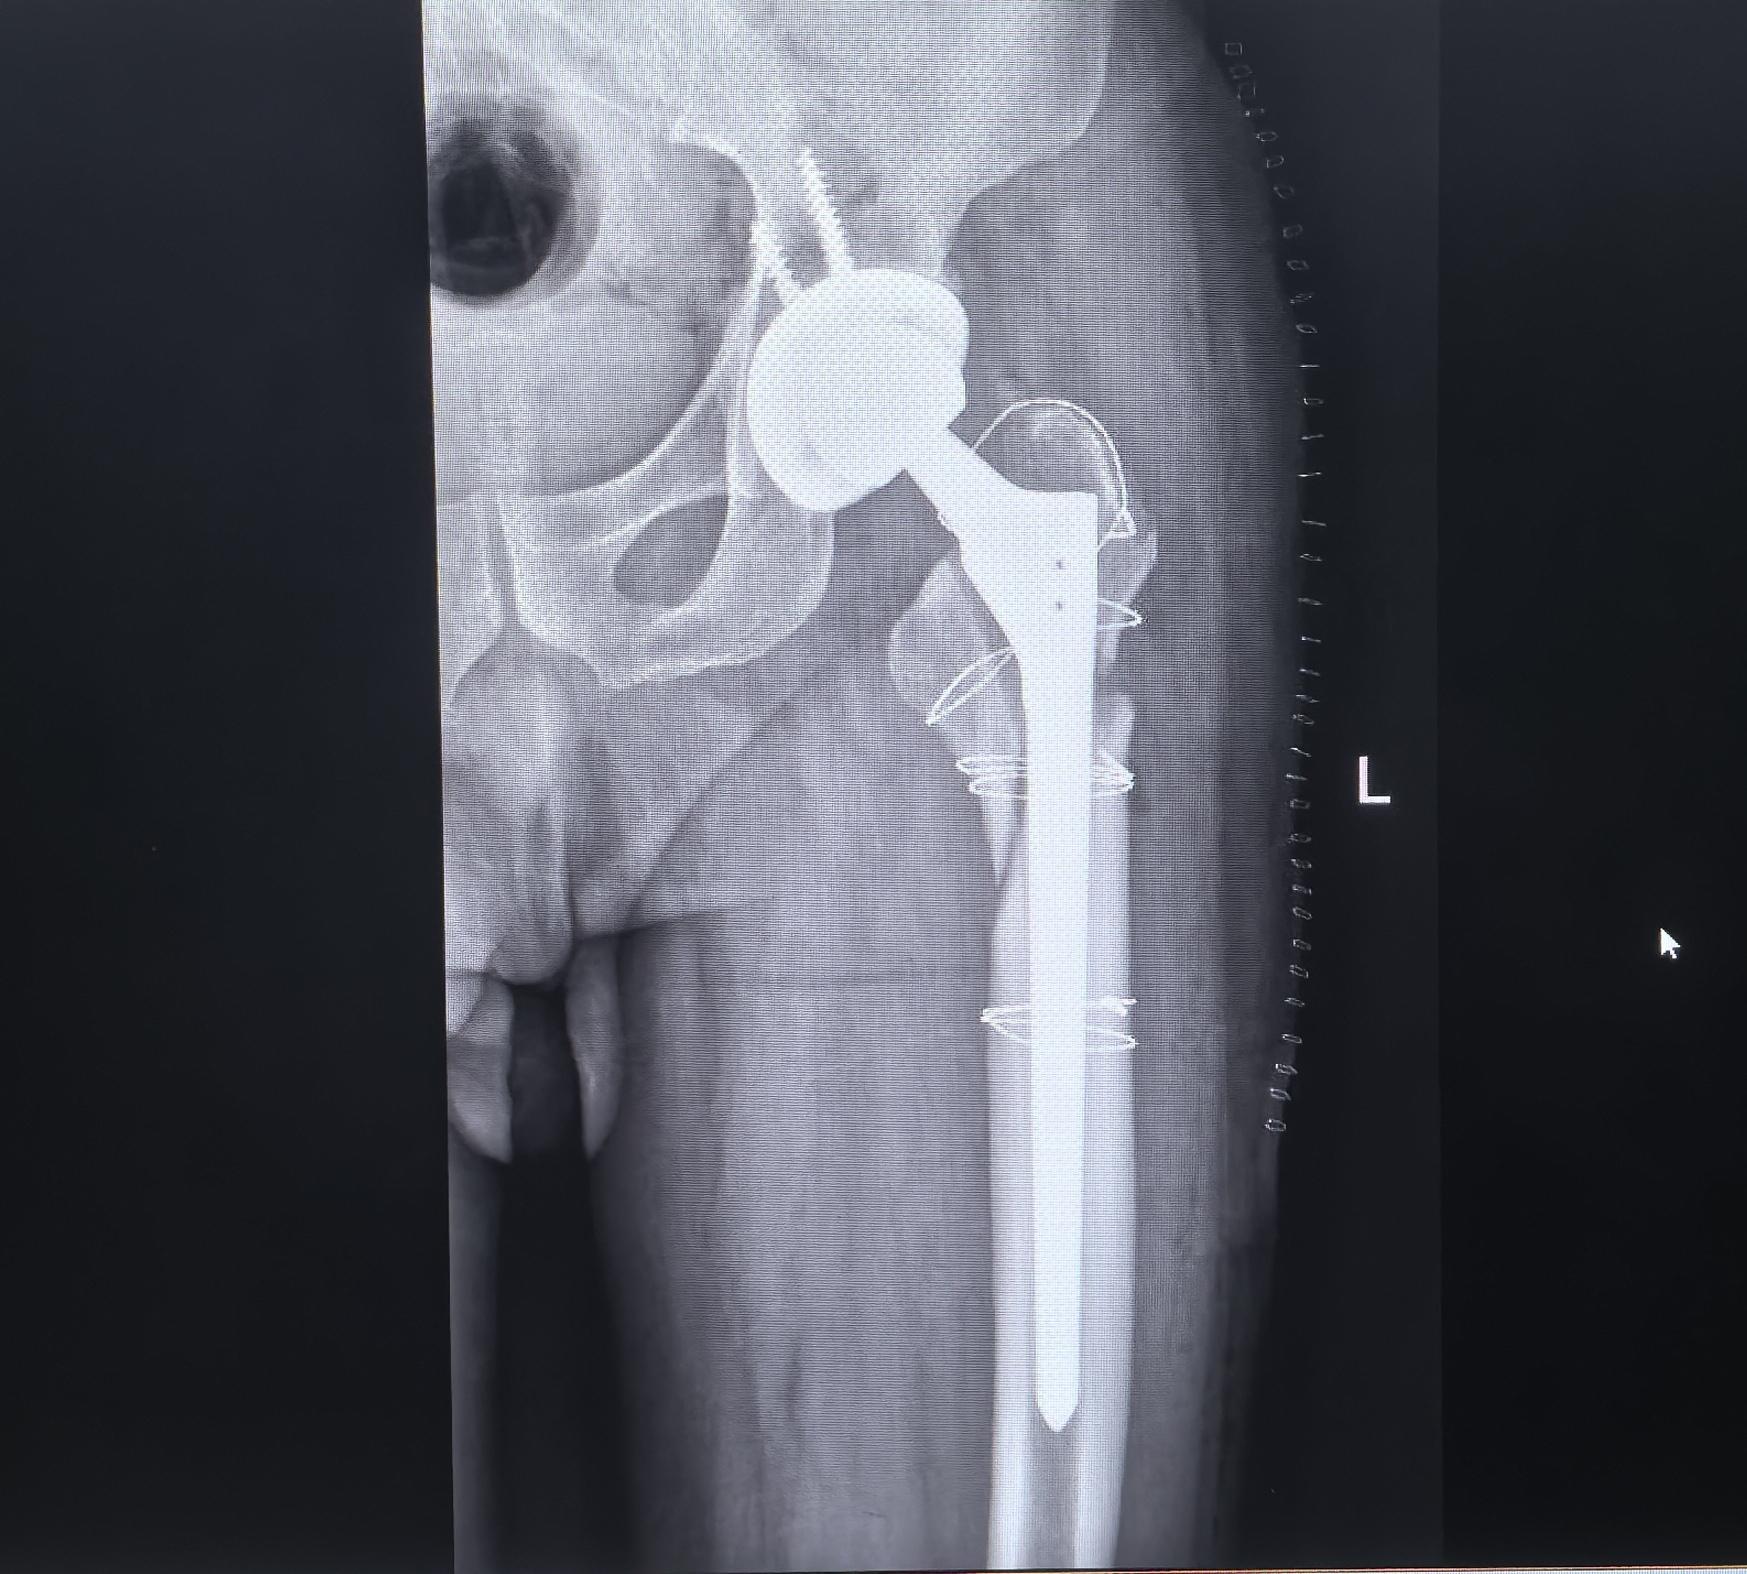

髋关节翻修。老年人要注意两个问题:1、防止跌倒;2、抗骨质疏松。假体周...